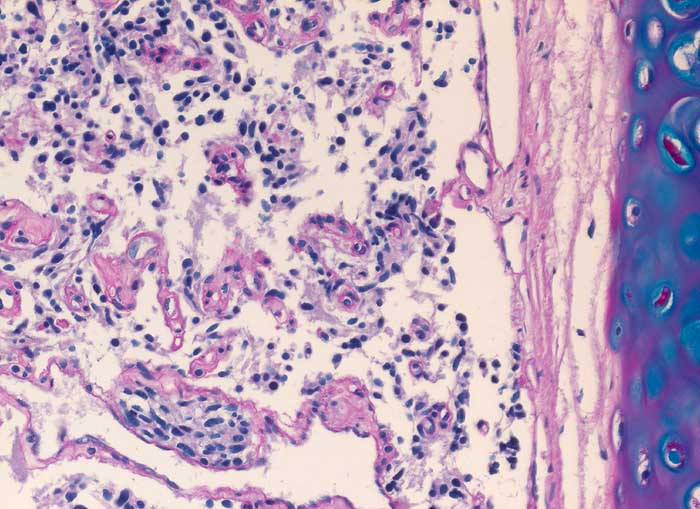

pit/ Typisches Karzinoid der Lunge

Typisches Karzinoid der Lunge

Die Diagnose hoch differenzierter neuroendokriner Tumoren ist schwierig, da ihre Oberfläche meist von Bronchialschleimhaut oder Bronchialepithel bedeckt ist und sie deswegen kaum Zellen abschilfern. Ausserdem sind die Atypien sehr diskret. Die Zellkerne sind rundlich bis oval, glatt begrenzt, fein granuliert und haben grosse Ähnlichkeit mit den Kernen von Flimmerzellen. Ohne Kenntnisse des klinischen Befundes sind Karzinoidzellen deshalb kaum von Basal- und Flimmerzellen zu unterscheiden. Der Zytoplasmasaum ist schmal und zerfällt leicht. Solche nackt liegenden Kerne können mit einem Lymphom verwechselt werden. Das typische Karzinoid hat eine sehr gute Prognose, kann aber in seltenen Fällen metastasieren. Die Unterscheidung von typischem und atypischem Karzinoid erfolgt am histologischen Schnitt durch Nachweis von Nekrosen und mehr als 3 bis 10 Mitosen pro HPF bei letzterem.